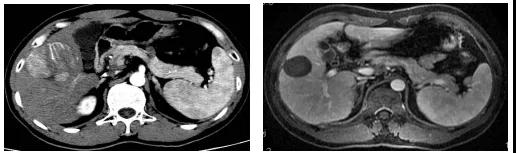

图1、病例54岁,肝右叶5.5×5.4cm肝癌(左图),行TACE+消融肿瘤完全坏死并缩小(右图),现患者已生存14年。